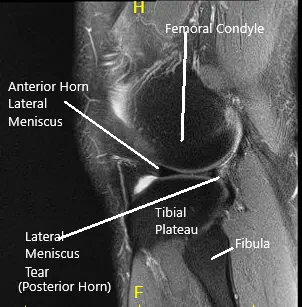

La resonancia magnética de la rodilla izquierda sugirió un desgarro meniscal lateral… Hubo una pérdida leve de cartílago de grosor parcial a lo largo del surco troclear central y en el compartimento lateral.

Resonancia magnética de rodilla en secciones coronal y sagital